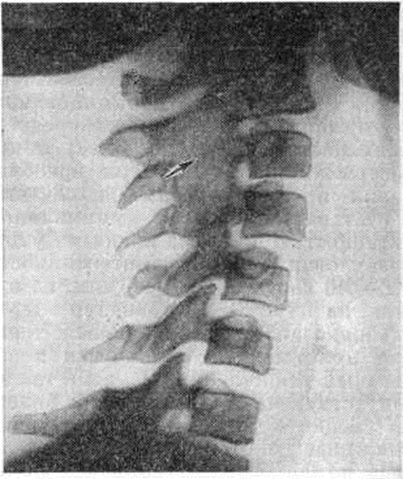

При ювенильном Ревматоидный артрит реже отмечается артрит мелких суставов кистей и стоп. Примерно у 1/3 больных наблюдается вовлечение межпозвоночных суставов шейного отдела позвоночника (особенно СII—СIII) с болями и ограничением движений. Часто отмечается артрит височно-нижнечелюстных суставов (смотри полный свод знаний). Примерно у 25% больных обычно через несколько лет от начала заболевания при рентгенологическое исследовании выявляется сакроилеит (смотри полный свод знаний). В целом деструкция суставного хряща и прилежащих отделов костей и деформации суставов развиваются при ювенильном Ревматоидный артрит значительно медленнее, чем при Ревматоидный артрит у взрослых.

Рис. 11. | ||

При ювенильном Ревматоидный артрит наблюдаются те же рентгенологическое изменения, что и при Ревматоидный артрит Характерно более частое, чем при Ревматоидный артрит, развитие артрита мелких суставов шейного отдела позвоночника, иногда с исходом в анкилоз (рисунок 11), и нарушения нормального хода развития скелета: ускорение роста трубчатых костей поражённой конечности или, наоборот, недоразвитие отдельных костей (например, нижней челюсти).